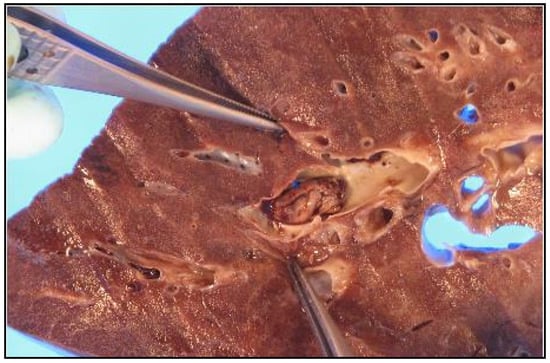

5. Other Gross Pathological Findings in COVID-19